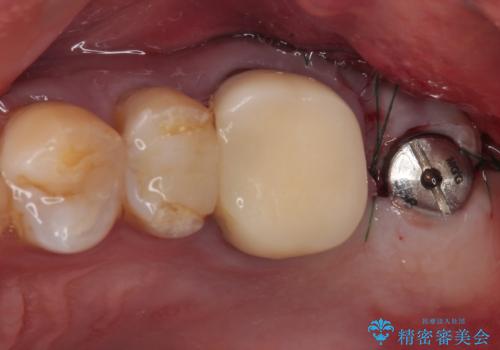

欠損した奥歯 インプラントによる補綴治療

- 破損したクラウンと、奥歯の欠損を気にして来院された患者様です。

奥歯の欠損部はインプラントによる補綴治療を、手前の破損したクラウンは作り替えをご希望でした。

しかしながら、レントゲンやCT画像から、手前の破損したクラウンの根尖部に大きな病変が認められ、インプラント埋入部にまで病変が及んでいることから、まずは手前の根管治療を行い、病変の正体を確認した後にインプラント埋入を行うこととしました。

口があまり開かず、インプラントの埋入角度がやや斜めとなりましたが、機能的には全く問題なく治療を終えることができました。